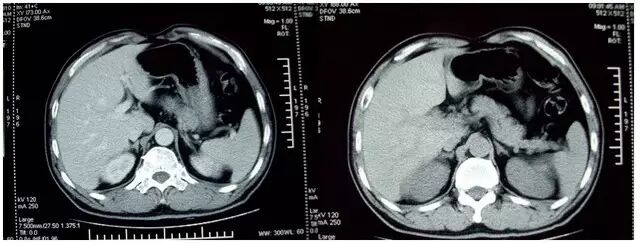

实验室检查:血、尿、粪常规、血糖、血脂和肝肾功能和甲状腺功能均正常, 血磷酸肌酸激酶明显升高为 470U/L(正常范围:38-147U/L)(低血钾可导致横纹肌的损伤);血钾 2.1 mmol/L,血钠 147 mmol/L,血氯 108 mmol/L;24 h 尿钾 79.2 mmol/24 h; 血气分析 PH7.44,标准碳酸氢根 27.1 mmo/L(正常范围:22-26 mmo/L),碱剩余 3 mmol/L,提示为代谢性碱中毒;血浆醛固酮 7.9ng/dl(低血钾可抑制醛固酮的分泌),血浆肾素活性 0.07ng/ml/h,醛固酮/肾素活性比值 (ARR)= 7.9/0.07 = 113,远大于 30。肾上腺 CT 显示「双侧肾上腺增生」(见图 1 )。建议患者进行双侧肾上腺静脉取血测醛固酮,但患者及家属不同意做创伤性检查。

图 1. 左图:右侧肾上腺增生;右图:左侧肾上腺增生